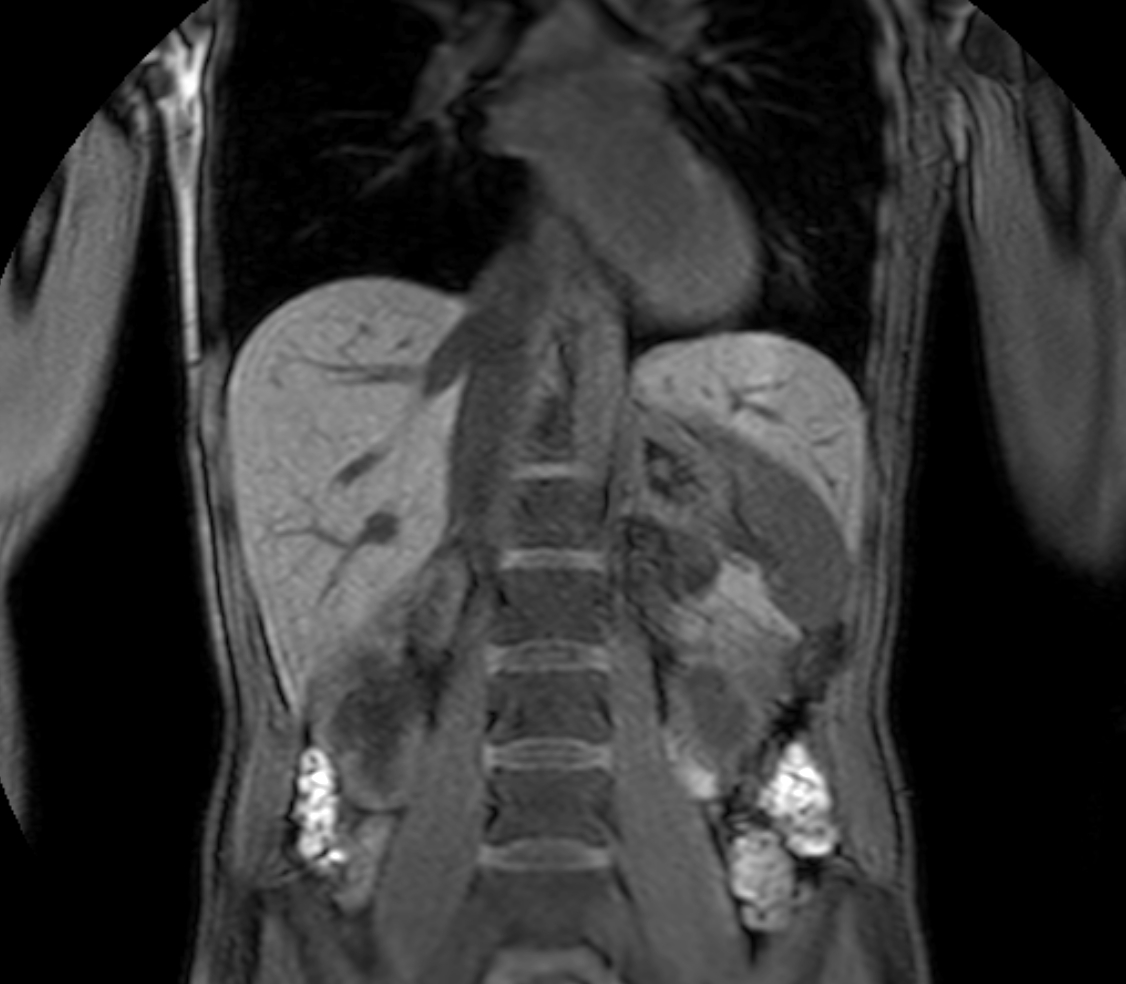

Coronal T2w TSE